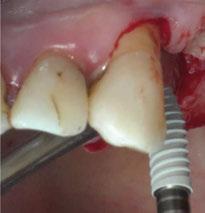

3. Fase quirúrgica final

A los 6 meses de cicatrización, se realizó un nuevo CBCT, obteniendo un nuevo archivo DICOM que alineamos con el STL del encerado. De esta manera, se planificó la posición de los implantes a 4 mm del margen de la restauración final y se diseñó y confeccionó la férula de cirugía guiada dentosoportada en 12-13 y 22-23, la cual imprimimos con la impresora 3D Formlabs®. El provisional

de carga inmediata lo diseñamos con el programa de diseño 3D Exocad® a partir del encerado y se imprimió también en clínica con la misma impresora 3D (Figuras 14-16).

La cirugía se realizó bajo sedación consciente y anestesia local (articaína 4% con epinefrina 40/0,01 mg/ml Ultracain®, 5 carpules en vestibular y palatino de la arcada superior). En primer lugar, se realizaron las exodoncias de los dientes remanentes 11, 21 y 24 y, a continuación, se adaptó la férula de cirugía guiada dentosoportada, insertando los implantes elegidos, en este caso en las posiciones 11 y 21 de Zimvie Tapered Screw-Vent Z3D de 3,7 por 13 mm, 14 Zimvie Tapered Screw-Vent Z3D de 3,7 por 13 mm y 16, 24 y 26 de Zimvie Tapered Screw-Vent Z3D de 4,7 por 13 mm, quedando todos ellos a un torque mayor a 30 Nm. Posteriormente, se realizaron el resto de exodoncias,

Figura 14. Férula de cirugía guiada para inserción de implantes.

Figura 19. Fresado para inserción de implantes.

Figura 18. Posicionamiento y verificación de férula en cirugía de implantes.

Figura 17. Exodoncias de 11 y 21 previo a inserción de férula cirugía guiada.

produciéndose la fractura de la tabla vestibular del 23, la cual se fijó con un tornillo de osteosíntesis, tras abrir un colgajo mucoperióstico. A continuación, se procedió al relleno de los alveolos que harán de pónticos y los gaps con GEISTLICH BIO-OSS® COLLAGEN 100 mg.

Seguidamente, se colocaron los pilares cónicos TSV-TM de Zimmer® y se atornillaron los pilares provisionales de titanio (Figuras 17-23).